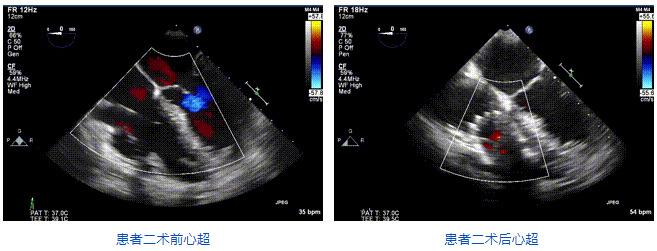

2021年12月24日,復(fù)旦大學(xué)附屬中山醫(yī)院葛均波院士團隊成功應(yīng)用LuX-Valve Plus為一例極重度三尖瓣反流(TR)合并房顫、房缺的患者完成了經(jīng)血管三尖瓣置換術(shù),這是在前基礎(chǔ)上,本周完成的第三例經(jīng)血管三尖瓣置換手術(shù),葛均波院士、周達新教授等與心外科魏來教授、賴顥教授,心超室的潘翠珍教授、李偉教授及麻醉科的郭克芳教授共同完成了本周手術(shù),均獲得圓滿成功!患者術(shù)后超聲顯示無TR,臨床癥狀明顯改善。本周手術(shù)的成功也為LuX-Valve Plus救治性臨床研究添上了濃墨重彩的一筆。

三例患者入院后,葛均波院士團隊周達新教授、潘文志教授、張源博士、陳莎莎博士及心超室的潘翠珍教授、李偉教授對患者的情況進行詳細評估和討論,最終決定為三例患者選擇LuX-Valve Plus40mm、50mm和50mm型號的瓣膜進行手術(shù)治療。手術(shù)后即刻拔除氣管插管,術(shù)后患者三尖瓣反流癥狀得到顯著改善,復(fù)查心超結(jié)果顯示人工三尖瓣瓣膜支架固定穩(wěn)定,瓣葉關(guān)閉形態(tài)未見異常,未見明顯反流。